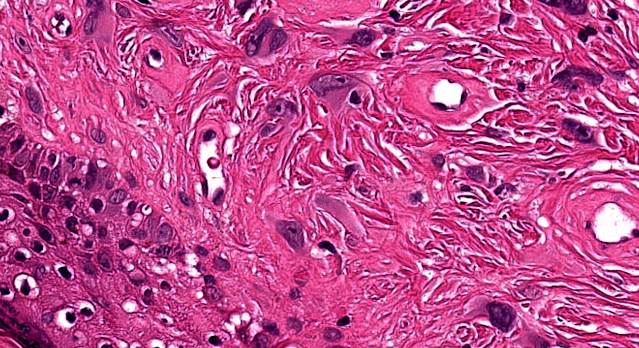

Dermatopathology Case 264 Get link Facebook X Pinterest Email Other Apps September 11, 2022 A 40 year woman with a lesion on the nose. Answer Get link Facebook X Pinterest Email Other Apps Comments